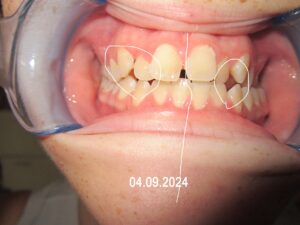

Dies sind Beispielbilder einer gelungenen kieferorthopädischen Behandlung: links war das Gebiss zu Beginn der Behandlung: die Fronthähne stehen schräg, die Nasenscheidewand stand schief, die Zahnmitte verlief nicht in einer geraden Linie, Die Eckzähne stehen schief.

Nach der Behandlung war die Zahnmitte durchgehend in der Mitte, die Nasescheidewand war gerade, die Eckzähne stehen, wie sie sollen.

Dadurch hat sich die folgende kieferorthopädische Behandlung um ca. 2 Jahre verkürzt. Die erzählte die Erziehungsberechtigte in der letzten Therapieeinheit.